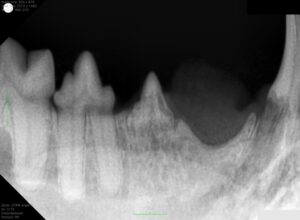

↑画像中央の歯と、右端に映る犬歯に吸収病巣が発生しているレントゲン画像です。

歯の表面が虫食い状に溶けている部分があり、歯根部は顎の骨と一体化しつつあります(骨性癒合)。